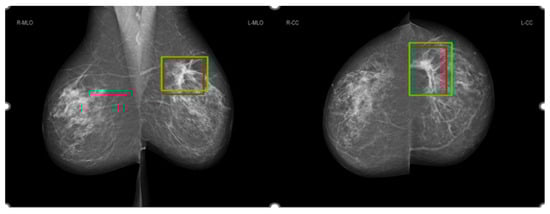

3.3. Comparison of Salience Maps on Original and Locally Enhanced Mammographic Images